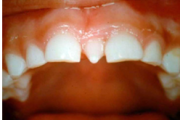

Puudub ülemine tsentraalne intsisiiv, kuid külgmised lõikehambad on juba lõikunud.

Puudub ülemine tsentraalne intsisiiv